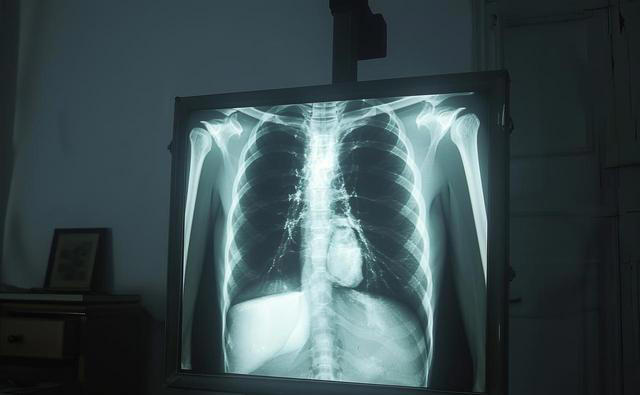

胸腹部CT显示右肺门有一处2.8厘米的占位性病变,而腿部的症状,正是肿瘤压迫神经和远处转移的信号。

诊断需结合胸部CT、骨扫描、肿瘤标志物等检查,必要时进行组织病理学活检。